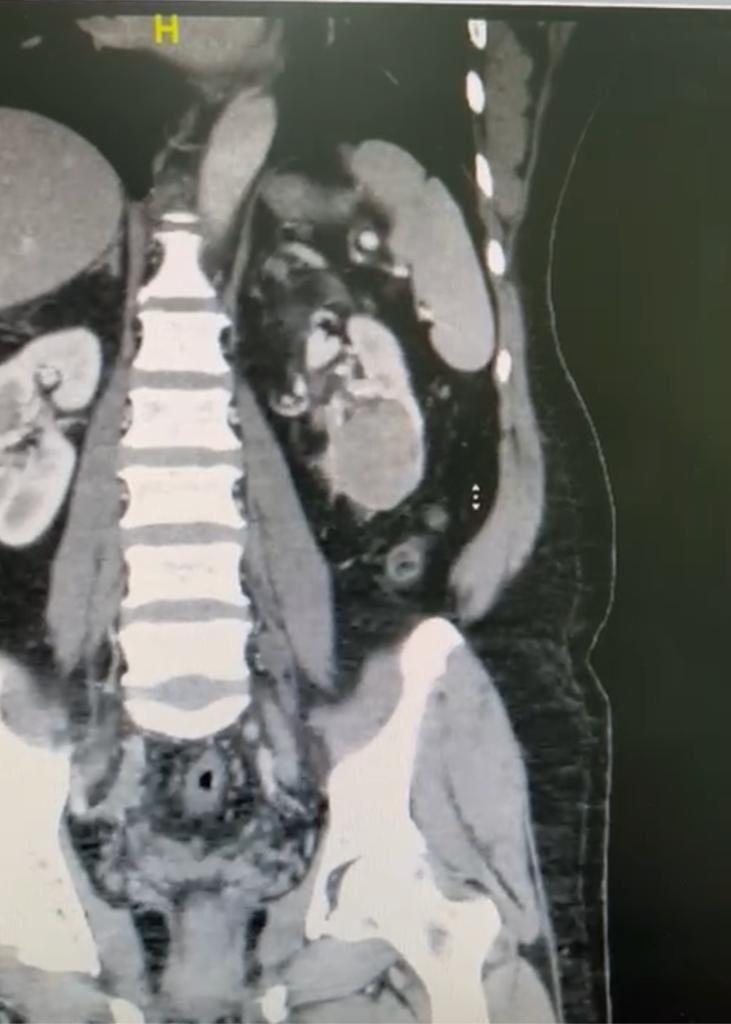

وأوضح "الدكتور محمد خان" أنه تمت مباشرة حالة المريض في عيادات المسالك البولية الخارجية، إذ خضع للفحص السريري وعمل كافة الفحوصات الطبية اللازمة من التحاليل المخبرية والأشعة المقطعية.

وأفاد بعد استكمال كافة الفحوصات الطبية اللازمة التي بينت نتائجها وجود ورم بحجم 7 سنتميتر في الكِلية اليسرى، حيث اتضح وجود الورم في معظم الكِلية اليسرى للمريض، الأمر الذي استدعى تحضير المريض لنقله إلى قسم العمليات، حيث تقرر التدخل العاجل لإجراء عملية نوعية دقيقة بالمنظار الجراحي.